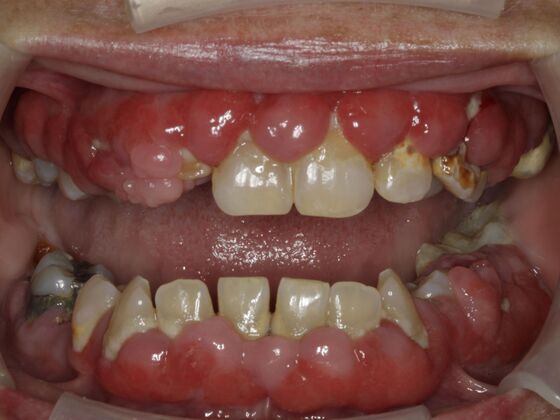

Smile Makeover & Veneers: Case 19

This may be one of the most difficult, yet rewarding cases I have ever done. A combination of meds for seizures and poor oral hygiene led to this painful, infected condition. She would not smile, talk to people, and was embarrassed. We thoroughly cleaned her teeth and performed laser, NON-surgical recontouring of her gums, removed several teeth and placed crowns, bridges and veneers to reach this end product. An amazing transformation that truly changed her life.